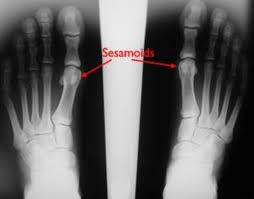

What Is Turf Toe - Confessions Of A Physio Who Knows Better Turf Toe Palermo Physiotherapy Wellness Centre Oakville : Even though it's linked to artificial surfaces found in most domed stadiums (hence its name), players can get turf toe on grass, as well as any other firm surface.. Turf toe is an injury of the first metatarsophalangeal(mtp) articulation, due to hyperextension of the big toe. This damage can occur when pushing down on the what is turf toe and how do you treat it? A turf toe taping technique will support and protect the toe preventing it from bending in the direction that will stress the ligament causing pain. The name turf toe comes from the fact that this injury is especially common among athletes who play on artificial turf. Turf toe is a sprain of the big toe joint resulting from injury during sports activities and usually results from excessive upward bending of the big toe.

Doctors call this injury turf toe because it appears more often in athletes playing on artificial turf. An athlete who suffers from this condition may complain of pain around the ball of the foot, particularly on the bottom. Turf toe is an injury of the first metatarsophalangeal(mtp) articulation, due to hyperextension of the big toe. What are possible complications of turf toe? Turf toe injury best treatment! This can cause you to sprain or injure your toe and the ligaments that surround it. Even though it is not considered a serious injury it can be very debilitating and take a long time to heal. Turf toe is a common sports injury that occurs when the bones and tissue around the big toe become damaged.

— written by bethany cadman on october 22, 2018. Turf toe is an injury of the first metatarsophalangeal(mtp) articulation, due to hyperextension of the big toe. A common athletic injury from field sports. An athlete who suffers from this condition may complain of pain around the ball of the foot, particularly on the bottom. Turf toe is a sprain of the fibrous joint capsule that supports the metatarsophalangeal (mtp) joint at the base of the big toe. We look at common causes, symptoms & treatment a turf toe injury develops when the big toe is bent too far back into hyperextension, most commonly when front of the foot is fixed to the ground, the. Turf toe is essentially a sprain or hyperextension of the toe. Suspect you have turf toe? It occurred more frequently in american football players after artificial turf became more common on playing fields. Taping will also help protect the ligament when returning to full fitness, especially if the ligament has been overstretched causing joint laxity. An injury where the big toe bends back too far aka metatarsophalangeal joint sprain. There are three grades of turf toe, 1 being the least serious and 3 being the most serious. No matter what grade of toe injury, the joint still.

— written by bethany cadman on october 22, 2018. The medical term for turf toe is a metatarsophalangeal (mtp) joint sprain of the big toe. The term turf toe was first coined by bowers and martin1 in a 1976 article describing capsuloligamentous sprains at the first metatarsophalangeal joint sustained by collegiate football players on artificial turf. The ligaments that connect the big toe to the ball of the foot are complex, and are essential to the moves involved in walking, running while turf toe is caused by constant or sudden hyperextension of the toe ligaments, the likelihood of this happening is increased when athletes train. Turf toe can be mild or severe depending on the injury grade.

We look at common causes, symptoms & treatment a turf toe injury develops when the big toe is bent too far back into hyperextension, most commonly when front of the foot is fixed to the ground, the. What are possible complications of turf toe? It happens most often in football players, but it can happen in other sports and activities as well. Turf toe can be mild or severe depending on the injury grade. Turf toe can range from a mild injury with only minor ligament damage to a chronic injury involving inflammation of the joint capsule and progressive cartilage formation and. The name turf toe comes from the fact that this injury is especially common among athletes who play on artificial turf. Learn the causes, symptoms and treatments for this common toe injury. A sprain to the first metatarsophalangeal(mtp) joint , otherwise known as a 'turf toe' or 'death toe' , is a common injury in athletes in which the plantar capsule and the ligament of first metatarsophalangeal joint is damaged. Turf toe is a common sports injury that occurs when the bones and tissue around the big toe become damaged. Doctors call this injury turf toe because it appears more often in athletes playing on artificial turf. Discover what turf toe is at 10faq health and stay better informed to make healthy living decisions. An athlete who suffers from this condition may complain of pain around the ball of the foot, particularly on the bottom. Even though it's linked to artificial surfaces found in most domed stadiums (hence its name), players can get turf toe on grass, as well as any other firm surface.

A physician will typically diagnose turf toe based on an athlete's symptoms, sports history, and a physical examination of the injured toe joint. Even though it's linked to artificial surfaces found in most domed stadiums (hence its name), players can get turf toe on grass, as well as any other firm surface. It is seen at all levels of competition, even among professional athletes. Most athletes suffering from this sports injury will recall exactly when and how the injury happened. Artificial turf is a harder surface than grass and does not have much give when forces are placed on it. It happens most often in football players, but it can happen in other sports and activities as well. A turf toe taping technique will support and protect the toe preventing it from bending in the direction that will stress the ligament causing pain. A sprain to the first metatarsophalangeal(mtp) joint , otherwise known as a 'turf toe' or 'death toe' , is a common injury in athletes in which the plantar capsule and the ligament of first metatarsophalangeal joint is damaged. The term turf toe was first coined by bowers and martin1 in a 1976 article describing capsuloligamentous sprains at the first metatarsophalangeal joint sustained by collegiate football players on artificial turf. Turf toe is a sprain of the main joint of the big toe. What are possible complications of turf toe? Turf toe happens when you bend your big toe up toward the top of your foot too far. A turf toe injury can damage any part of the plantar complex, causing mild to more severe injuries.